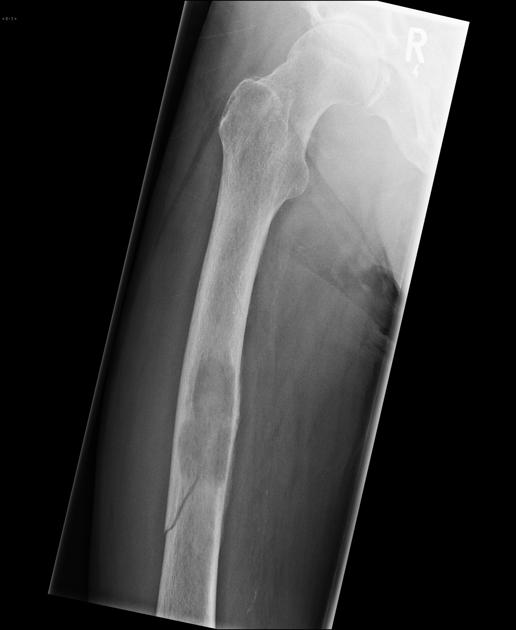

Pathologic Fracture

Occurs in bones already weakened by a pre-existing condition.

Comminuted Fracture

The bone is broken into 3 or more fragments - common in long bones such as the femur

Spiral/Torsion Fracture

The break coils around the bone - common in femur fractures

Bone Cyst

Wall of fibrous tissue filled with fluid - they are asymptomatic - appears as a lucent, oval shape with the long axis parallel to the host bone

The most common benign bone tumor - arises from the growth zone between the epiphysis and diaphysis of long bones (Metaphysis). Most commonly involves the lower femur or upper tibia and is capped by growing cartilage. Many time it is asymptomatic unless the affected long bone is traumatized which results in a pathologic fx. of the diseased bone.

Osteochondroma (Exostosis)